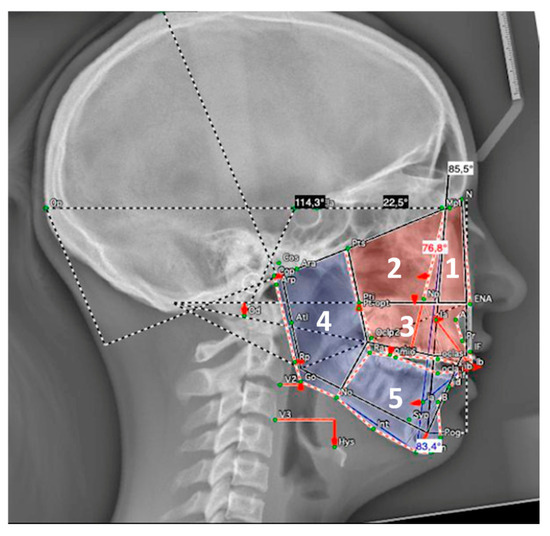

Background: The aims of the study were to describe facial morphology and analyze facial growth in adolescents with Robin sequence (RS) or Stickler syndrome. Methods: The facial morphology, mandibular size, and facial growth of 69 adolescents (ages 12–18) with RS were analyzed using existing cephalometric radiographs (n = 37) and photographs (n = 69). All participants were followed in our institution since birth. None underwent growth-modifying treatment for micrognathia during infancy, but all had conservative orthodontic treatment during adolescence. Results: Cross-sectional cephalometric analysis according to Tweed revealed differences in RS adolescents as compared with reference values, such as a proportionate retrusion of both jaws, as indicated by decreased SNA and SNB angles (p < 0.05). This finding was mostly associated with skeletal Class I (62.2%) and a vertical facial pattern as indicated by increased FMA and CoGoMe angles (p < 0.05). In Delaire’s analysis, patients showed decreased maxillary, maxillary alveolar (p < 0.05), and mandibular body territories (p > 0.05) but increased ramus (p > 0.05) and nasopremaxillary territories (p < 0.05). According to Ricketts’ analysis, mandibular width was decreased in half of our patients (p > 0.05). The mandibles were harmoniously downsized before and after the growth spurt (p < 0.05); however, they exhibited greater growth velocities than controls. A long-term study during puberty revealed an increase in SNB angles and a decrease in ANB angles (both p < 0.05), which improved the maxillomandibular relationship. Additionally, the vertical facial pattern attenuated (FMA, SNGoGn, and CoGoMe angles decreased; p > 0.05). On cross-sectional photographic analysis, 33.3% of patients had an orthofrontal (straight), 59.4% a cisfrontal (convex), and 7.3% a transfrontal (concave) profile. Their vertical facial proportions were normal. In the subjective profile analysis, most patients (approximately 84%) had good or acceptable profiles, with no major deficit of chin projection. The initial degree of neonatal retrognathia and type of cleft palate surgery did not affect major skeletal parameters (p > 0.05). However, the degree of neonatal functional impairment affected the vertical parameters (SNGoGn, FMA angle; p < 0.05). Conclusions: Overall, RS patients presented a bi-retrognathic profile, a normal jaw relationship, and a tendency toward a vertical growth pattern. Partial mandibular catch-up growth occurred during the pubertal growth spurt. The degree of neonatal retrognathia does not predict further mandibular growth. Full article